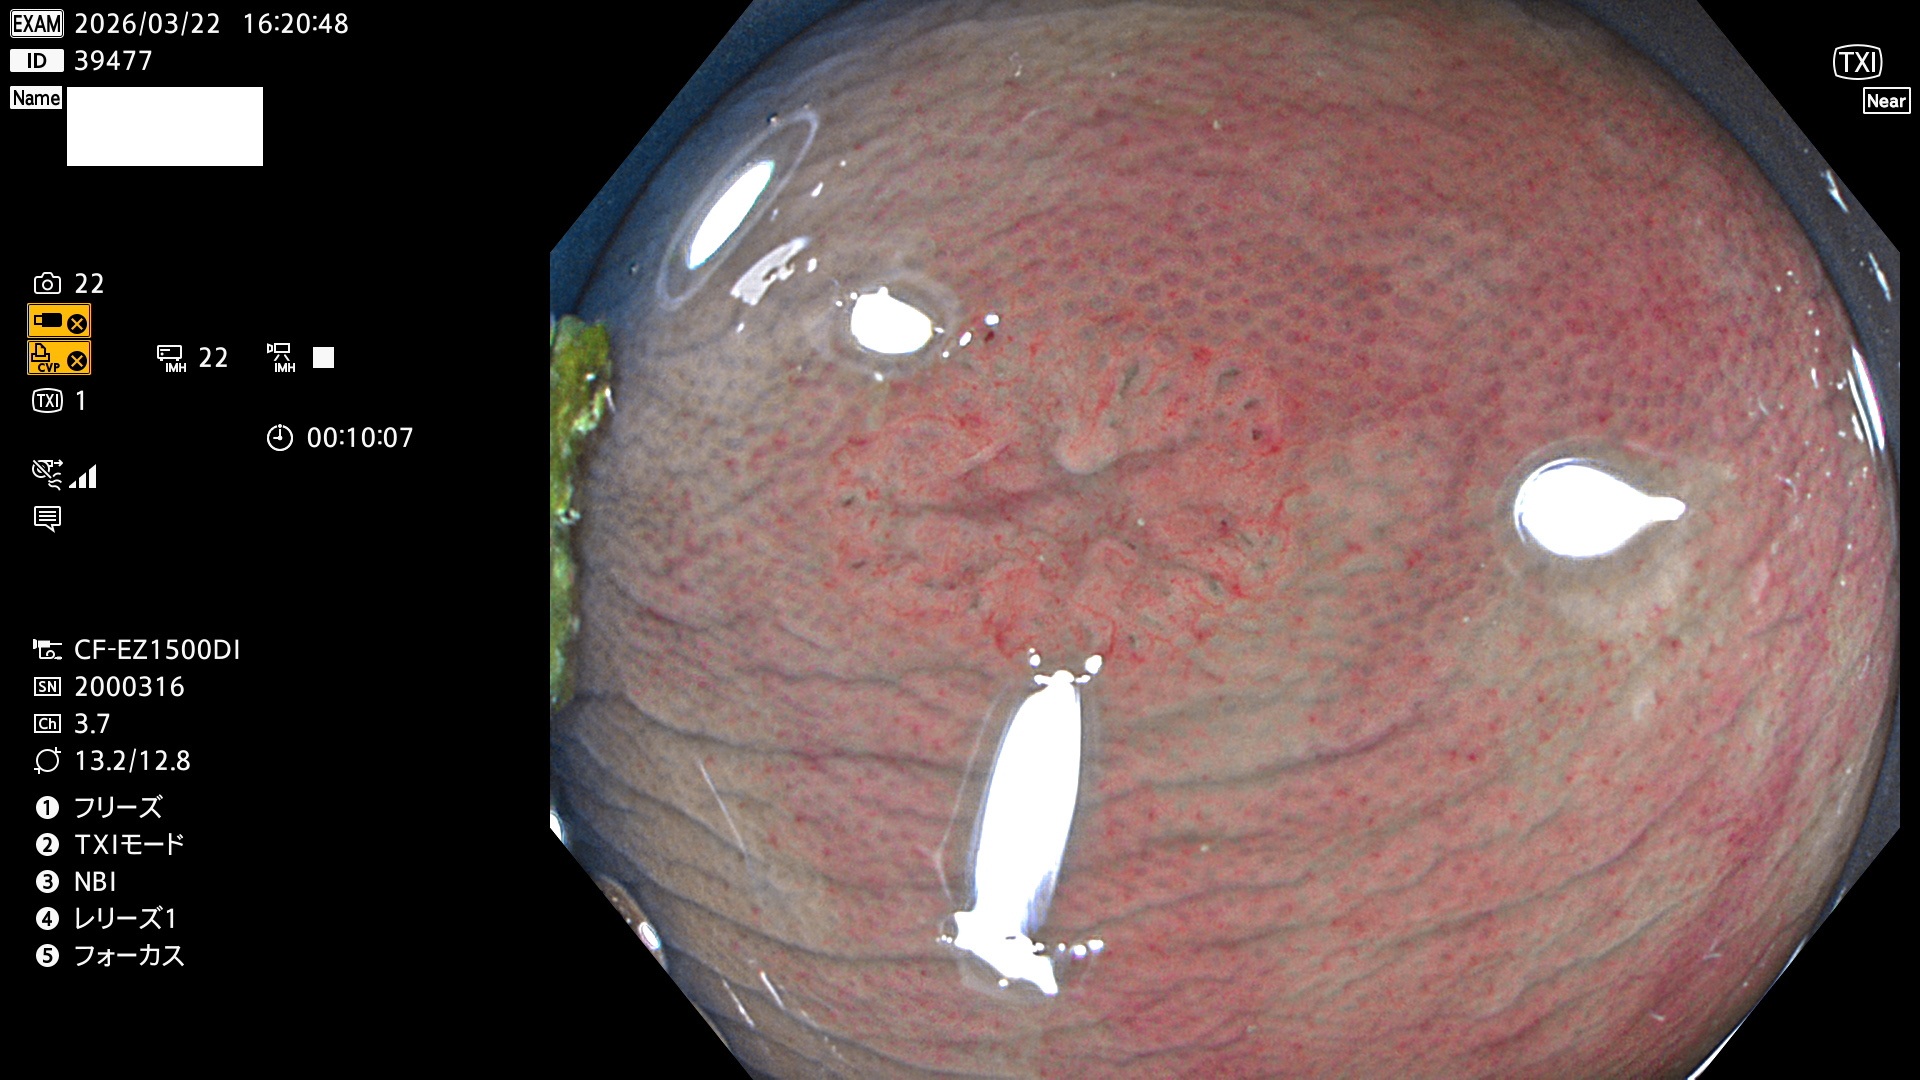

完全に平坦な物をUb、陥凹している物をUcと呼びます。Ubは認識が困難で、Ucはびらん(炎症)と紛らわしいために見落とされやすく、「内視鏡後・大腸癌」の原因になります。

毎週の検査(木・金・土・日)に発見されたUbとUc型・腺腫を、その週の日曜の夜にUPし1週間、提示します。

2026年3月19日〜3月22日の4日間(40件)4個 (Uc_ADR=4個/40人=10%)